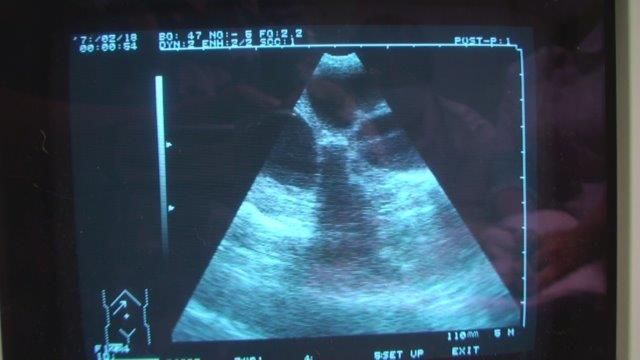

7歳 腹部膨満、食欲不振で来院 エコーで水がたまった臓器が多数みられる

診断 レントゲン検査、エコー検査で子宮内の液体や粘液の貯留を確認する。